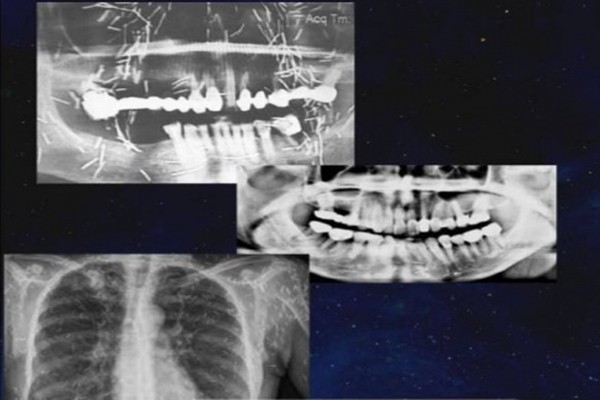

Nữ bệnh nhân đột quỵ, bác sĩ phát hiện chuyện ghê rợn. Bác sĩ phát hiện bệnh nhân này cấy rất nhiều "kim bùa" vào mắt, mặt, cổ và ngực khi kiểm tra kết quả chụp CT, máu và chụp X-quang của bệnh nhân.

Tuy nhiên, một bác sĩ ở Malaysia chia sẻ, anh từng gặp một nữ bệnh nhân bị đột quỵ, liệt và không thể nói được. Sau nhiều lần kiểm tra, bác sĩ phát hiện ra số lượng lớn "kim bùa" (hay còn gọi là kim quyến rũ) được cấy vào cơ thể người phụ nữ, bao gồm cả mặt, cổ và ngực. Thế nhưng khi bị phát hiện, người phụ nữ vẫn không chịu lấy kim ra, cuối cùng tử vong.

Khi kiểm tra kết quả chụp CT, máu và chụp X-quang của bệnh nhân, bác sĩ phát hiện bệnh nhân này cấy rất nhiều kim bùa vào mắt, mặt, cổ và ngực.

Theo bác sĩ Razif, khi còn làm việc tại bệnh viện ở Kedah, anh gặp một người phụ nữ khoảng 60 tuổi nhập viện do đột quỵ, bị liệt một bên cơ thể, không nói được nhưng vẫn tỉnh táo và phản ứng nhanh khi được gọi.

"Tôi không biết điều gì đã đầu độc tâm trí cô ấy. Các con cô ấy chắc chắn không biết chuyện này nhưng vì quy định của bệnh viện tôn trọng ý muốn của bệnh nhân, tôi không thể nói với các con cô ấy bất cứ điều gì. Tôi rất hy vọng bệnh nhân sẽ đồng ý loại bỏ hết số kim tích tụ trong người nhưng cô ấy không đồng ý. Sau khi bệnh nhân tử vong, tôi hối hận vì đã không nói cho con của bệnh nhân biết tường tận sự việc", bác sĩ Razif nói.

Theo tìm hiểu, ở Malaysia, thứ gọi là kim bùa có tên chính thức là Susuk hay kim quyến rũ, là những chiếc kim làm bằng vàng hoặc kim loại quý khác, được cắm vào các mô mềm của cơ thể để hoạt động như những lá bùa. Susuk có nhiều mục đích khác nhau, từ thẩm mỹ thuần túy đến điều trị đau khớp và các bệnh nhỏ khác.

Về vấn đề này, nhiều bác sĩ đã để lại bình luận, cho biết họ đã từng gặp những trường hợp như vậy, phần lớn là phụ nữ, không chỉ cấy kim vào mặt mà những người này còn cấy vào chân, bụng.